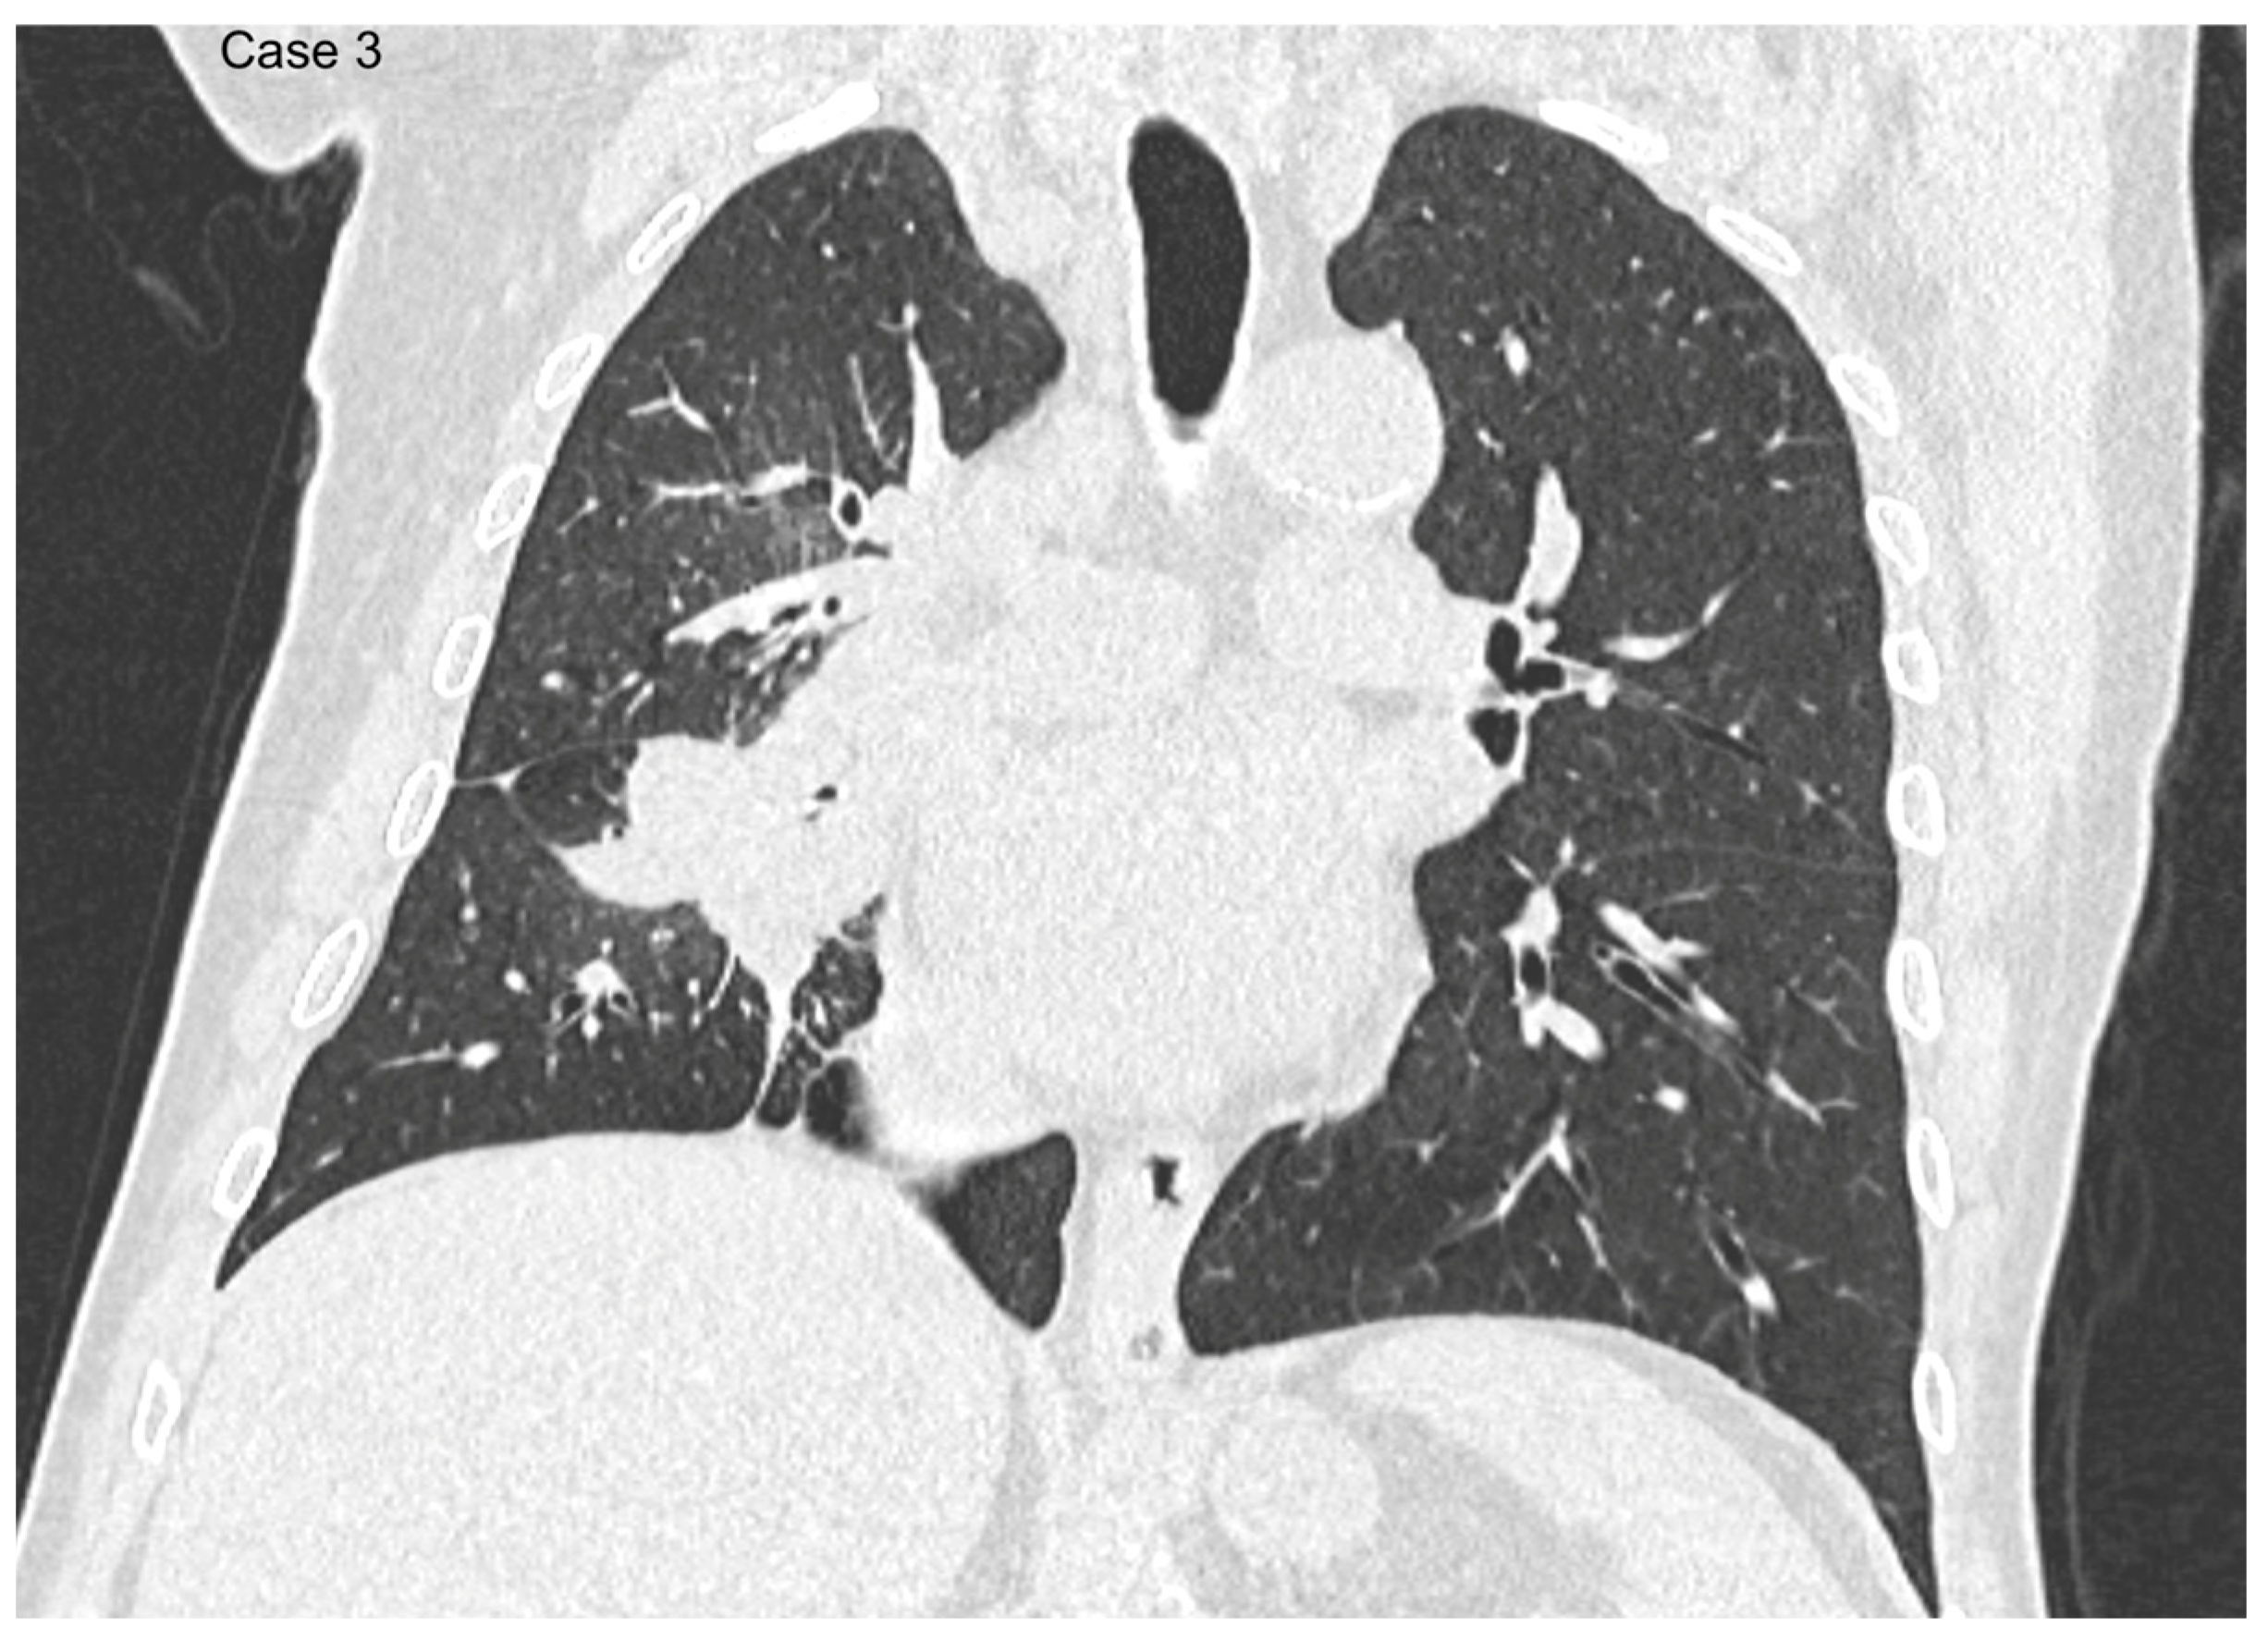

2.2. Data Collection and Imaging Evaluation

2.3. Staging Procedures